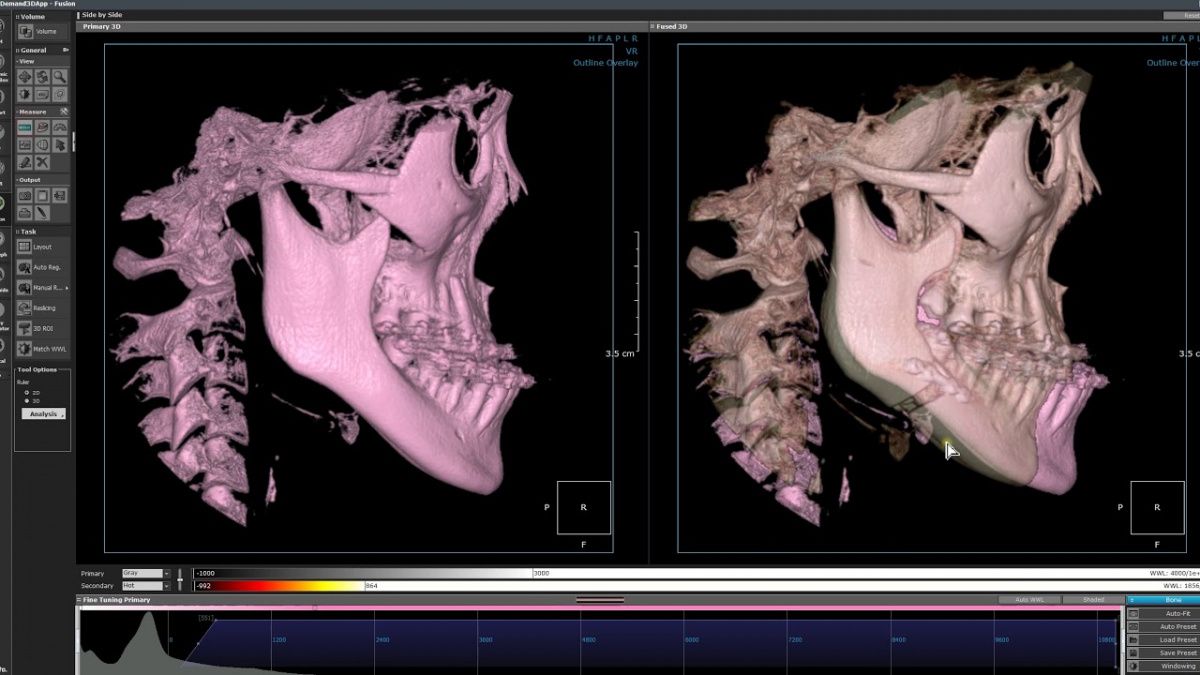

Немаловажным, а может главным вопросом, является универсальность программы-просмотровщика, в которой будут работать врачи-стоматологи. У Papaya 3D есть два варианта программ: Triana и OnDemand3D. Оба просмотровщика обладают схожим интерфейсом и имеют самые важные опции, а именно:

• режим MPR (многоплоскостная реконструкция). Именно здесь выстраивается интересующий участок челюсти или зуба для анализа.

• панорамный реформат. Возможность постройки классической и сегментарной панорамы позволяет продемонстрировать план лечения пациенту, а также оценить расположение анатомических структур на боковых кросс-секциях.

• модуль дентальной имплантации. Возможность виртуальной установки дентального имплантата с анализом окружающей костной ткани. В библиотеке представлен широкий спектр имплантологических систем с индивидуальной прорисовкой имплантата.

• выделение нижнечелюстного канала позволяет продемонстрировать расположение важного анатомического образования и определить зону безопасности при проведении лечения.

• функции плотности, линейных измерений и угла – необходимы для получения полноценной информации для последующего лечения.

• 3D режим – показывает трехмерную модель челюсти с целью определения аномалий, деформация, а также визуализации виртуальных имплантатов.

triana3.jpg triana4.jpg triana5.jpg

OnDemand3D (1).jpg OnDemand3D (2).jpg OnDemand3D 1.jpg

Таким образом обе программы являются простыми в пользовании, но обладающими обширным спектром возможностей для диагностики любыми специалистами-стоматологами. В данные программы происходит загрузка классических файлов DICOM 3.0, которые являются общепринятым форматом записи данных пациента. Это важный момент, так как позволяют врачу, имеющему полную версию программы загружать даже сторонние исследования и просматривать их в этих программах. Простота в освоении этих программ позволяет даже специалисту, не работающему раннее с этими программами, быстро адаптироваться и получить качественную информацию. Возможность выгрузки STL-файла дополнительно создает возможность интегрировать данные с цифровым ортопедическим протоколом.